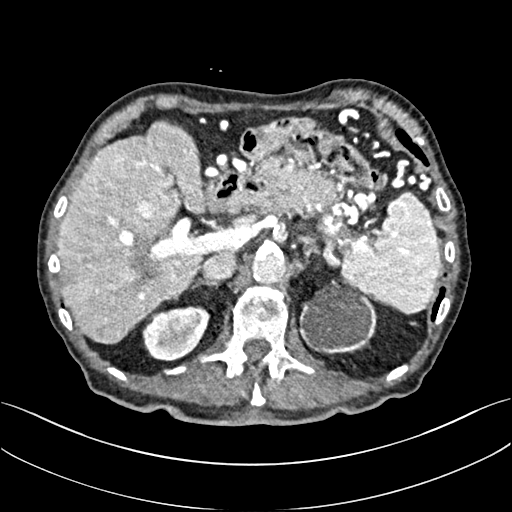

To demonstrate the effectiveness of the proposed network, we perform the qualitative comparisons over three representative abdominal images presented in Figs. 3, 5 and 7. For better evaluations of the image quality with different denoising models, zoomed regions-of-interest (ROIs) are marked by red rectangles and shown in Figs. 4, 6 and 8 respectively. Note that all results from different denoising models focus on two aspects: content restoration and noise-reduction. All CT images in axial view are displayed in the angiography window [-160, 240]HU.

The real NDCT images and corresponding LDCT images are presented in Figs. 3a and 3b. As observed, there are distinctions between ground truth (NDCT) images and LDCT images. Figs. 3a and 7a show the lesions/metastasis. Fig. 5a presents focal fatty sparing/focal fat. In Figs. 4a, 6a and 8a, these lesions can be clearly observed in NDCT images; in contrast, from Figs. 4b, 6b, and 8b, it can be seen that the original LDCT image is noisy, and lacks structural features for task-based clinical diagnosis. All adopted denoising models suppress noise to some extent.